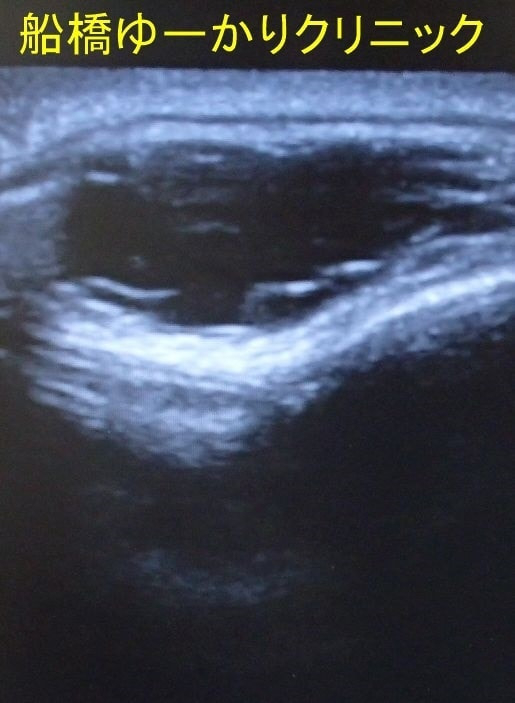

エコー

右こめかみのしこり。生まれつきで、徐々に増大。摘出組織には毛髪が含まれていました。

上腕のしこり。やや盛り上がって、薄い赤みがあります。エコーでは境界不明瞭な不均一な低エコー像。皮膚を紡錘形に切除し、皮下腫瘍を摘出しました。病理組織は皮膚線維腫でした。